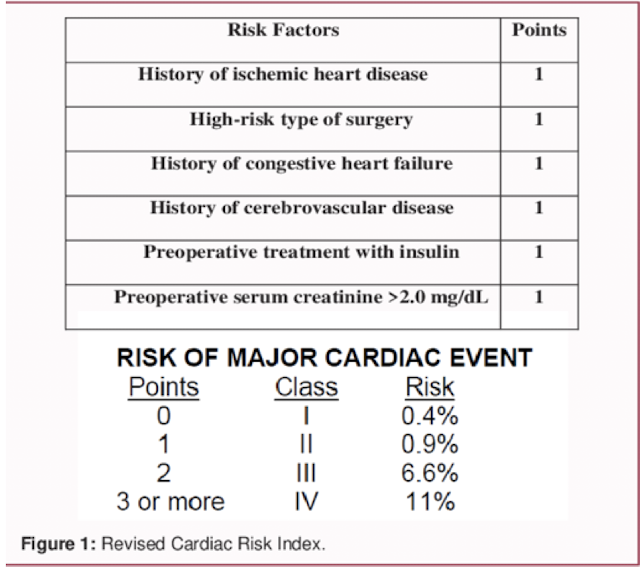

RCRI (Revised Cardiac Risk Index)

• Hx of ischemic heart disease

• Hx of CHF

• Hx of Cerebrovascular disease

• High-risk operation

• Preoperative treatment with insulin

• Preoperative serum creatinine >2.0mg/dl

Does this patient care increased risk for developing postoperative cardiac complications?